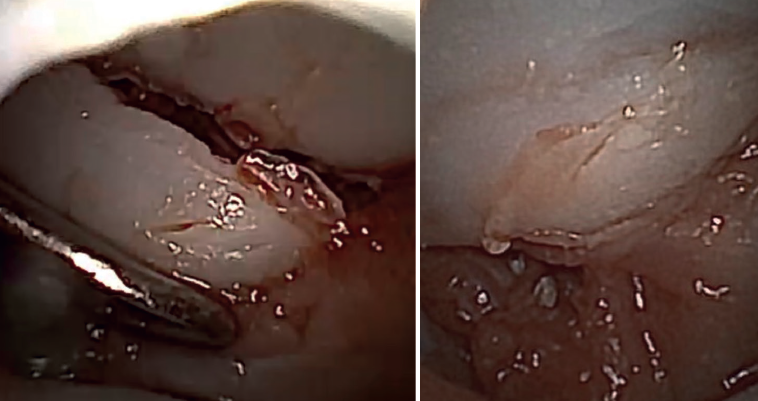

Arthroscopy of the MCP joint allows extensive visualization of the metacarpal head and the base of the proximal phalanx (Figure 1).

Figure 1. Arthroscopic visualization of the metacarpophalangeal joint of a third finger. At the top of the image we see the base of the P1 with the corresponding fracture line. The metacarpal head is shown at the bottom of the image.